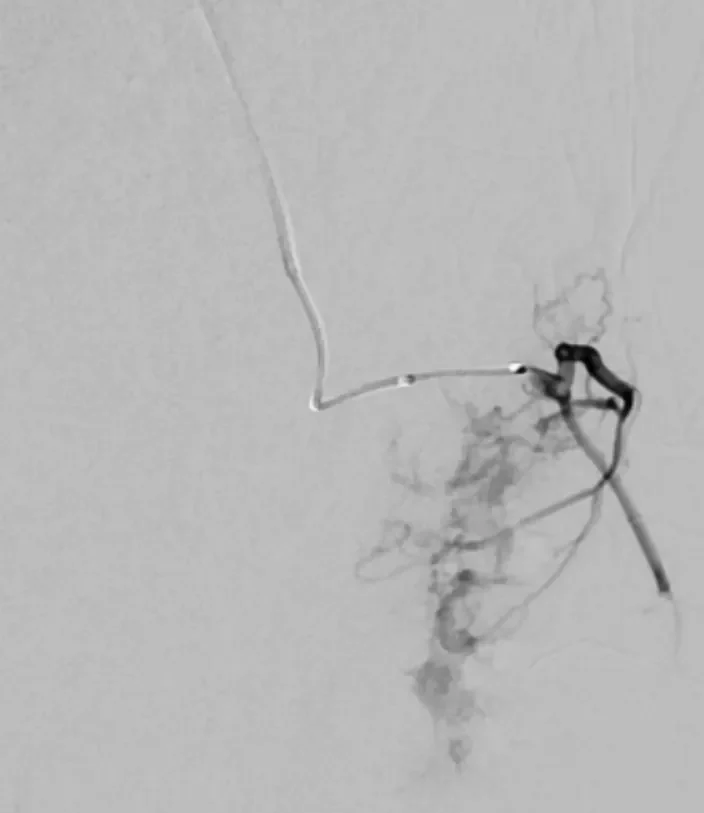

65 year old with a left femoral renal metastasis lesion. Angiograms showing vascularity of the lesion. The two annotated images show the tortuosity of the vessel supplying the lesion. The dotted orange coloured line shows the path of the vessel. It was not possible to cannulate this artery with conventional microcatheters.